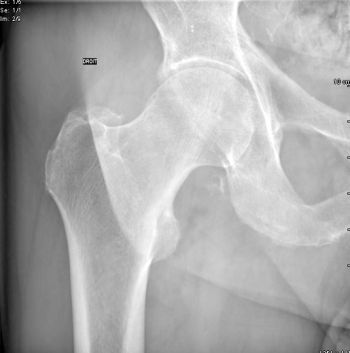

Qu'est ce qu'une radiographie ?

En quoi consiste l'examen ?

Une technique d'imagerie bien connue, et qui pourtant a aussi bénéficié de belles avancées technlogiques pour améliorer la qualité de l'image tout en baissant la dose de rayonnement, et en facilitant le travail des manipulateurs(trices).

• Principe

La technique utilise les rayons X, afin d'obtenir une projection  de la surface à radiographier.

La radiographie peut apporter une somme d'informations importantes

aux radiologues.Elle fait partie du bilan d'imagerie standard à réaliser, et va notamment apporter des informations sur la statique du patient ( images en station verticale), ce que l'imagerie en coupe ne permet pas.